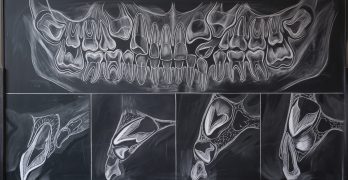

Caninos impactados: ¿Es hora de actualizar tu enfoque diagnóstico?

El artículo que compartimos hoy se llama Can Panoramic Radiography Reliably Detect Root Resorption From Impacted … [Leer más...] acerca de Caninos impactados: ¿Es hora de actualizar tu enfoque diagnóstico?

Consideraciones Clínicas para la Tracción de Múltiples Incisivos y Caninos Maxilares Impactados

artículo que compartimos el día de hoy se llama Cone-beam CT evaluation of orthodontic treatment outcomes for multiple … [Leer más...] acerca de Consideraciones Clínicas para la Tracción de Múltiples Incisivos y Caninos Maxilares Impactados